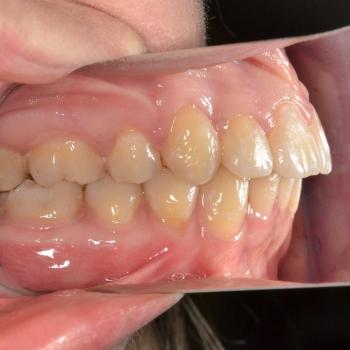

Luca saját elhatározásból, az alsó és felső fogív torlódása, de főleg a két felső szemfog ectopiás helyzete miatt keresett fel. Már elsőre pillantásra látható volt és Luca is sejtette, hogy foghúzások nélkül az Ő esete nem oldható meg,de szerencsére ez nem tántorította el a céljától.

Közös döntés eredményeként fém önligírozó fogszabályozót választottunk, illetve a felső kisőrlők, illetve egy darab alsó metszőfog eltávolítására került sor. Az alsó metszőfog eltávolítása elsőre szokatlannak tűnhet, de a fogszabályozásban ez bevett gyakorlat hiszen esztétikai problémát nem okoz és a húzás által biztosított plusz hely rögtön a megfelelő helyen áll a rendelkezésünkre.

A kezelés befejeztével minden felmerülő problémát és eltérést sikerült megoldanunk, így egy funkcionálisan és esztétikailag is szép eredményt kaptunk.